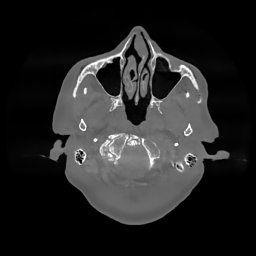

The results for simulated noisy data are shown in Fig. 2. The first and third rows display two representative slices from the test set, and the second and fourth rows present the corresponding error maps. The traditional WCE method suppresses cupping artifacts and recovers some missing anatomical structures but still shows noticeable deviations from the ground truth. Predictions from the four diffusion-based models demonstrate a markedly improved ability to restore anatomical structures. Among them, cDDPM fails to fully reconstruct the patient bed and retains residual noise in its outputs. This noise is attributable to an incomplete reverse denoising process rather than residual Poisson noise, as evidenced in our noise-free experiments (Fig. 5 in the Appendix). PatchDiffusion, diffusionGAN, and I2SB achieve similar visual quality, with I2SB producing the cleanest and most consistent reconstructions.

The experimental results on clinical head data are shown in Fig. 4. The reference images were reconstructed using the fast iterative shrinkage-thresholding algorithm (FISTA) with total variation regularization from non-truncated projection data. In the WCE reconstructions (Fig. 4(b)), severe truncation prevents accurate recovery of anatomical structures outside the FOV. Despite being trained solely on simulated data with a domain gap, all deep learning models can restore a substantial portion of the missing anatomy. Among them, the diffusion-based methods recover soft-tissue boundaries more faithfully than the conventional deep learning approach FBPConvNet, highlighting their stronger image generation capability. However, cDDPM reconstructions exhibit more noticeable noise than those from other methods, consistent with the simulated data results. The patchDiffusion model introduces artifacts within the FOV, likely due to its patch-wise processing strategy. While I2SB shares the same limitations as other diffusion models in perfectly restoring soft-tissue detail, it produces fewer residual noise patterns and fewer artifacts within the FOV boundaries. Overall, Fig. 4 demonstrates the strong efficacy of I2SB in reconstructing real CBCT data.